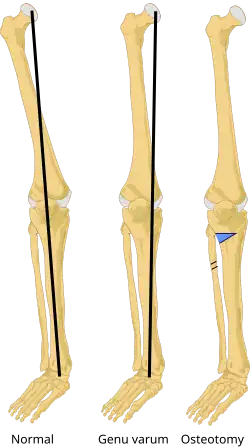

Genu varum (also called bow-leggedness, bandiness, bandy-leg, and tibia vara) is a varus deformity marked by (outward) bowing at the knee, which means that the lower leg is angled inward (medially) in relation to the thigh's axis, giving the limb overall the appearance of an archer's bow. Usually medial angulation of both lower limb bones (fibula and tibia) is involved.[1]

Valgus osteotomy. The black line is the mechanical axis. This process may be done to correct a varus deformity.

Generally, no treatment is required for idiopathic presentation as it is a normal anatomical variant in young children. Treatment is indicated when it persists beyond 3+12 years old. In the case of unilateral presentation or progressive worsening of the curvature, when caused by rickets, the most important thing is to treat the constitutional disease, at the same time instructing the care-giver never to place the child on their feet. In many cases, this is quite sufficient in itself to effect a cure, but matters can be hastened somewhat by applying splints. When the deformity arises in older patients, either from trauma or occupation, the only permanent treatment is surgery, but orthopaedic bracing can provide relief.